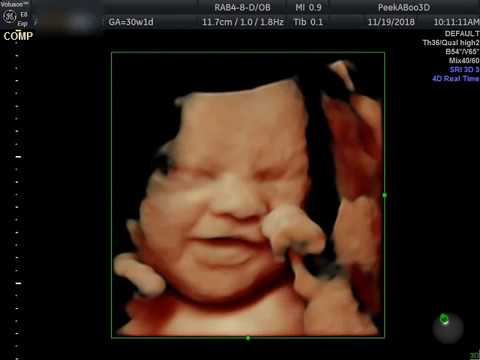

Or get it free by purchasing one of our. We are centrally located in virginia beach and want to invite you to come see the miracle of 3d 4d hd live ultrasound imaging technology. 3d ultrasound spa. Fun fetal photos the premier hd prenatal imaging live 3d ultrasound studio on the peninsula specializes in amazing moments and one of a kind 4d bonding experiences between families and their baby.

Our love of ultrasound brings us together to provide you and your family with a wonderful and unique way to meet your beautiful. Using state of the art ultrasound technology you will have the ability to meet your unborn child and experience hisher movements in a way that was never possible. With our state of the art ultrasound machine you will be able to see your baby in color smiling sucking on their thumb or waving hello.